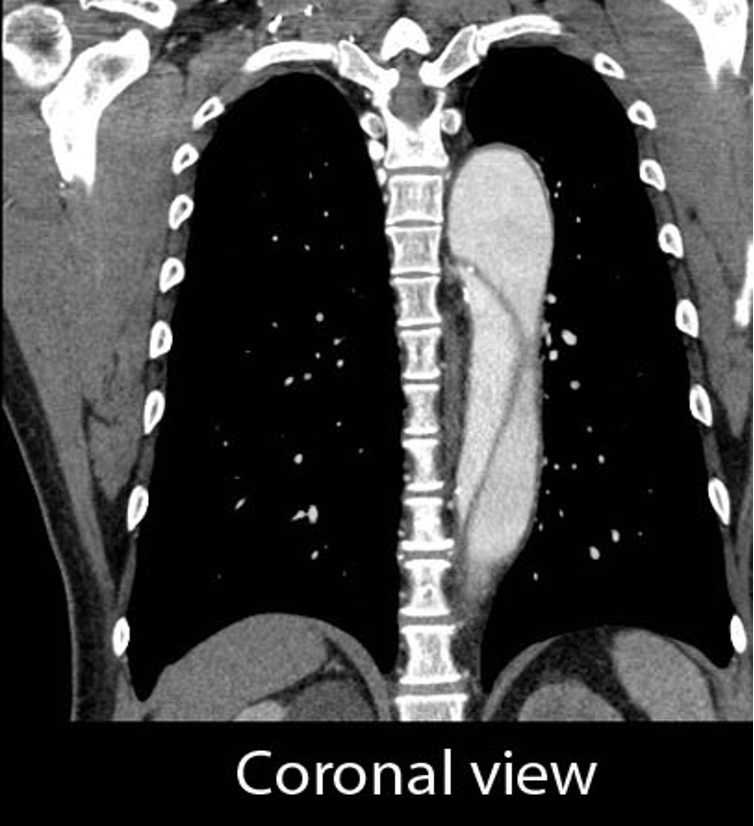

What does this coronal CT view refer to

Aortic Dissection